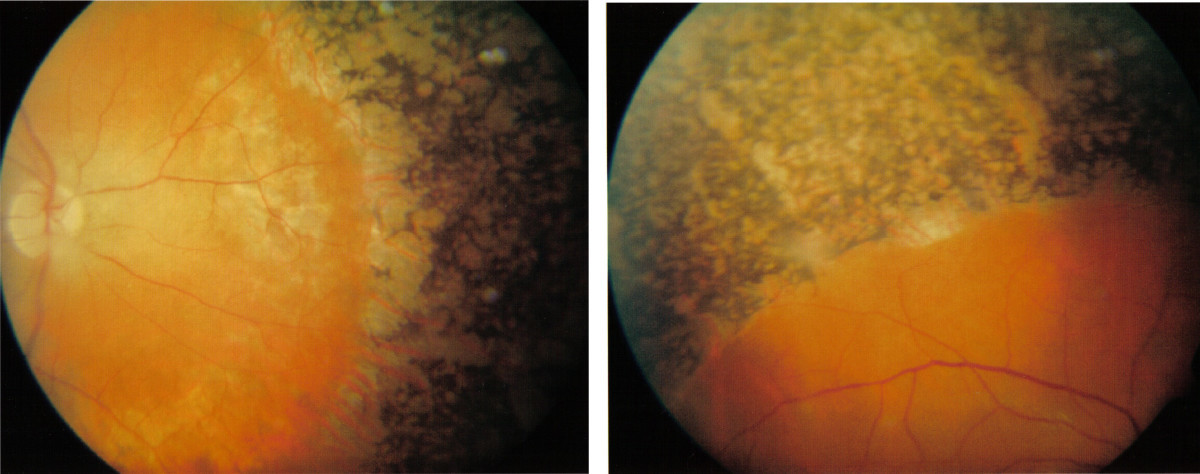

3 Refsum syndrome

Refsum syndrome

Refsum’s syndrome is an autosomal recessive disorder caused by mutations in phytanoyl-CoA hydroxylase. Clinically, patients have mild icthyosis, cerebellar ataxia, polyneuropathy, salt and pepper retinitis pigmentosa, sensorineural deafness, and arrhythmias with heart block. They are not overly sensitive to UV radiation.